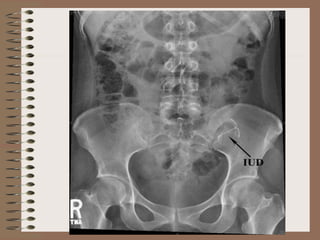

• Uterine perforation

– Most commonly with

• Wrong technique

• Wrong timing (between 48 hrs to 6 wks

postpartum)

– Detected by

• USG – Ideal

• X-ray

– Treatment – Removal of IUD